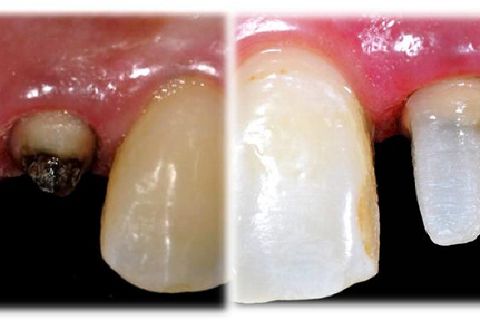

• Figura 1. Aspecto inicial do elemento 12 com redução extensa da porção coronária. Observa-se enfraquecimento e manchamento radicular, consequência de múltiplas substituições empregando núcleos metálicos fundidos. Indicou-se a reabilitação deste elemento empregando cimentação totalmente química de retentor reforçado com fibra de vidro e reconstrução coronária com resina composta para confecção de preparo para coroa total.

• Figura 7. Reconstrução da porção coronária com resina composta nano-híbrida Ice (SDI). Inserção incremental envolvendo o remanescente dental e retentor, planejando geometria do preparo para coroa total. Fotoativação de cada incremento por 40s.

• Figura 8. Aspecto inicial, e aspecto final do preparo para coroa total. Neste momento cabe ao profissional a adequação do preparo de acordo com o tipo de material constituinte da coroa total, ou seja, infra-estrutura metálica ou cerâmica reforçada.